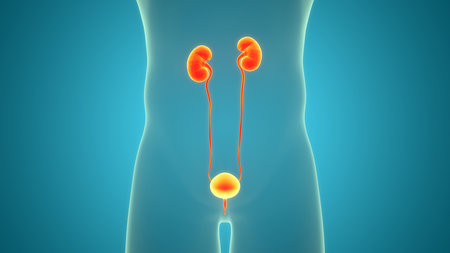

Human Urinary System Kidneys with Bladder Anatomy For Medical Concept 3D Illustration

3D Illustration Concept of Human Urinary System Kidneys with Bladder Anatomy

3D Medical Illustration Concept of Human Urinary System Kidneys with Bladder Anatomy

Human Urinary System Kidneys with Bladder Anatomy For Medical Concept 3D Illustration

3D Illustration Concept of Human Urinary System Kidneys with Bladder Anatomy

Human Urinary System Anatomy For Medical Concept 3D Illustration

3D Illustration Concept of Human Urinary System Kidneys with Bladder Anatomy

Human Urinary System Anatomy For Medical Concept 3D Illustration

3D Illustration Concept of Human Urinary System Kidneys with Bladder Anatomy

3D Illustration Concept of Human Urinary System Kidneys with Bladder Anatomy

3D Medical Illustration Concept of Human Urinary System Kidneys with Bladder Anatomy

3D Illustration Concept of Human Urinary System Kidneys with Bladder Anatomy

3D Illustration Concept of Human Urinary System Kidneys with Bladder Anatomy